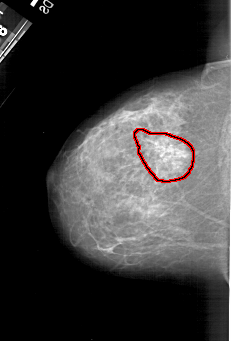

A_1217_1.LEFT_CC

LEFT_CC LINES 5791 PIXELS_PER_LINE 3916 BITS_PER_PIXEL 12 RESOLUTION 43.5 OVERLAY

FILE: A_1217_1.LEFT_CC.OVERLAY

TOTAL_ABNORMALITIES 1

ABNORMALITY 1

LESION_TYPE MASS SHAPE ARCHITECTURAL_DISTORTION MARGINS SPICULATED

ASSESSMENT 4

SUBTLETY 2

PATHOLOGY MALIGNANT

TOTAL_OUTLINES 1

BOUNDARY